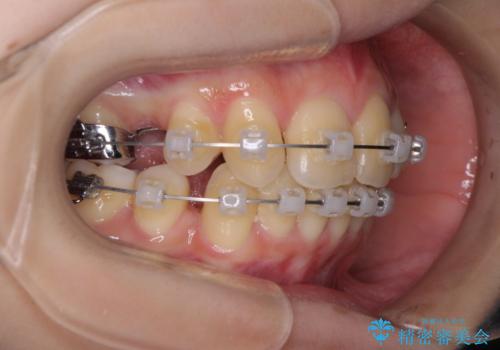

出っ歯を治したい ワイヤー装置による抜歯矯正

- クリアブラケット

- 上下の出っ歯を気にして来院された患者様です。

口元を積極的に引っ込めるために、上下左右の小臼歯を4本抜歯することとしました。

右上前から2番目の歯が欠損しているため、①矯正治療により欠損部にスペースを作りインプラント補綴を行って前歯を左右対称に揃える、②左右非対称となるが、欠損補綴を行わずに排列する、のいずれかとなりますが、患者様と相談の上②にて矯正治療を行うこととしました。

変則的な歯列であったため、奥歯がしっかりと咬み合うのか、前歯はしっかりと排列できるのかと不安ではありましたが、結果としてはきれいに整った歯列にて終了することができました。